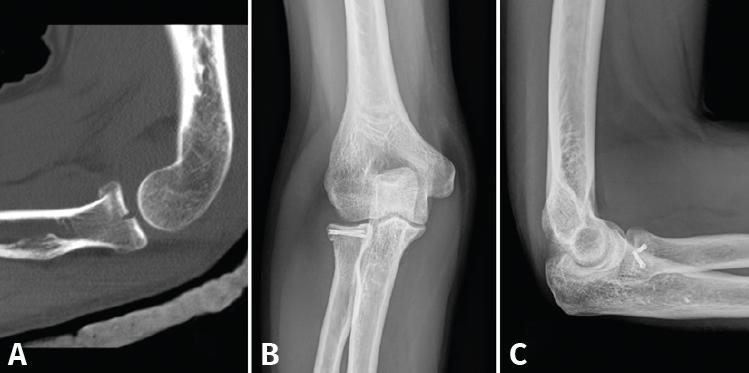

- Reducción abierta y fijación interna (RAFI): el objetivo es obtener una fijación anatómica y estable. Usaremos tornillos canulados de minifragmentos a compresión, sin cabeza, que dejaremos a nivel subcondral (Figura 3). Si existe afectación del cuello, lo ideal es sintetizar primero los fragmentos de la cabeza y añadir después algún tornillo hacia la diáfisis o una placa de bajo perfil (Figura 4)(13).

Figura 3. Ejemplo de fractura de Mason II tratada con 2 tornillos de minifragmentos canulados. A: imagen sagital en tomografía axial computarizada (TAC); B y C: radiografía anteroposterior y lateral de control a los 6 meses.

Figura 4. Proyección lateral de una fractura de cabeza y cuello de tipo Mason III, sintetizada con tornillos a compresión y una placa de bajo perfil.